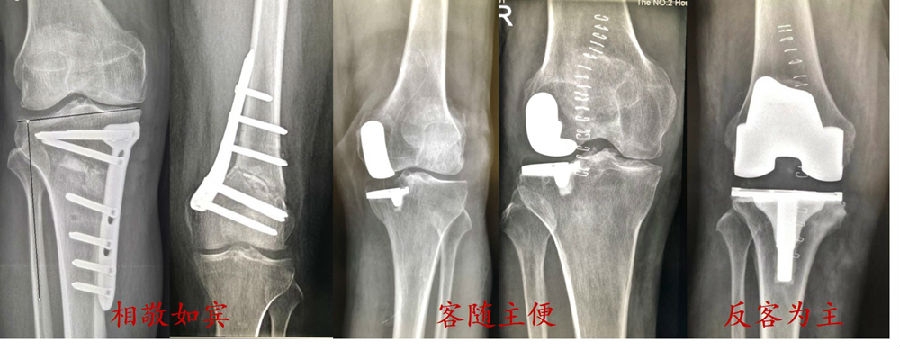

手术操作顺序:

股骨外侧闭合截骨11mm,恢复关节线方向(放平关节线LDFA:88°)。

胫骨侧闭合13mm,矫正下肢力线至目标力线(居中)。

术中

术中透视

术后X线片

术后1个月